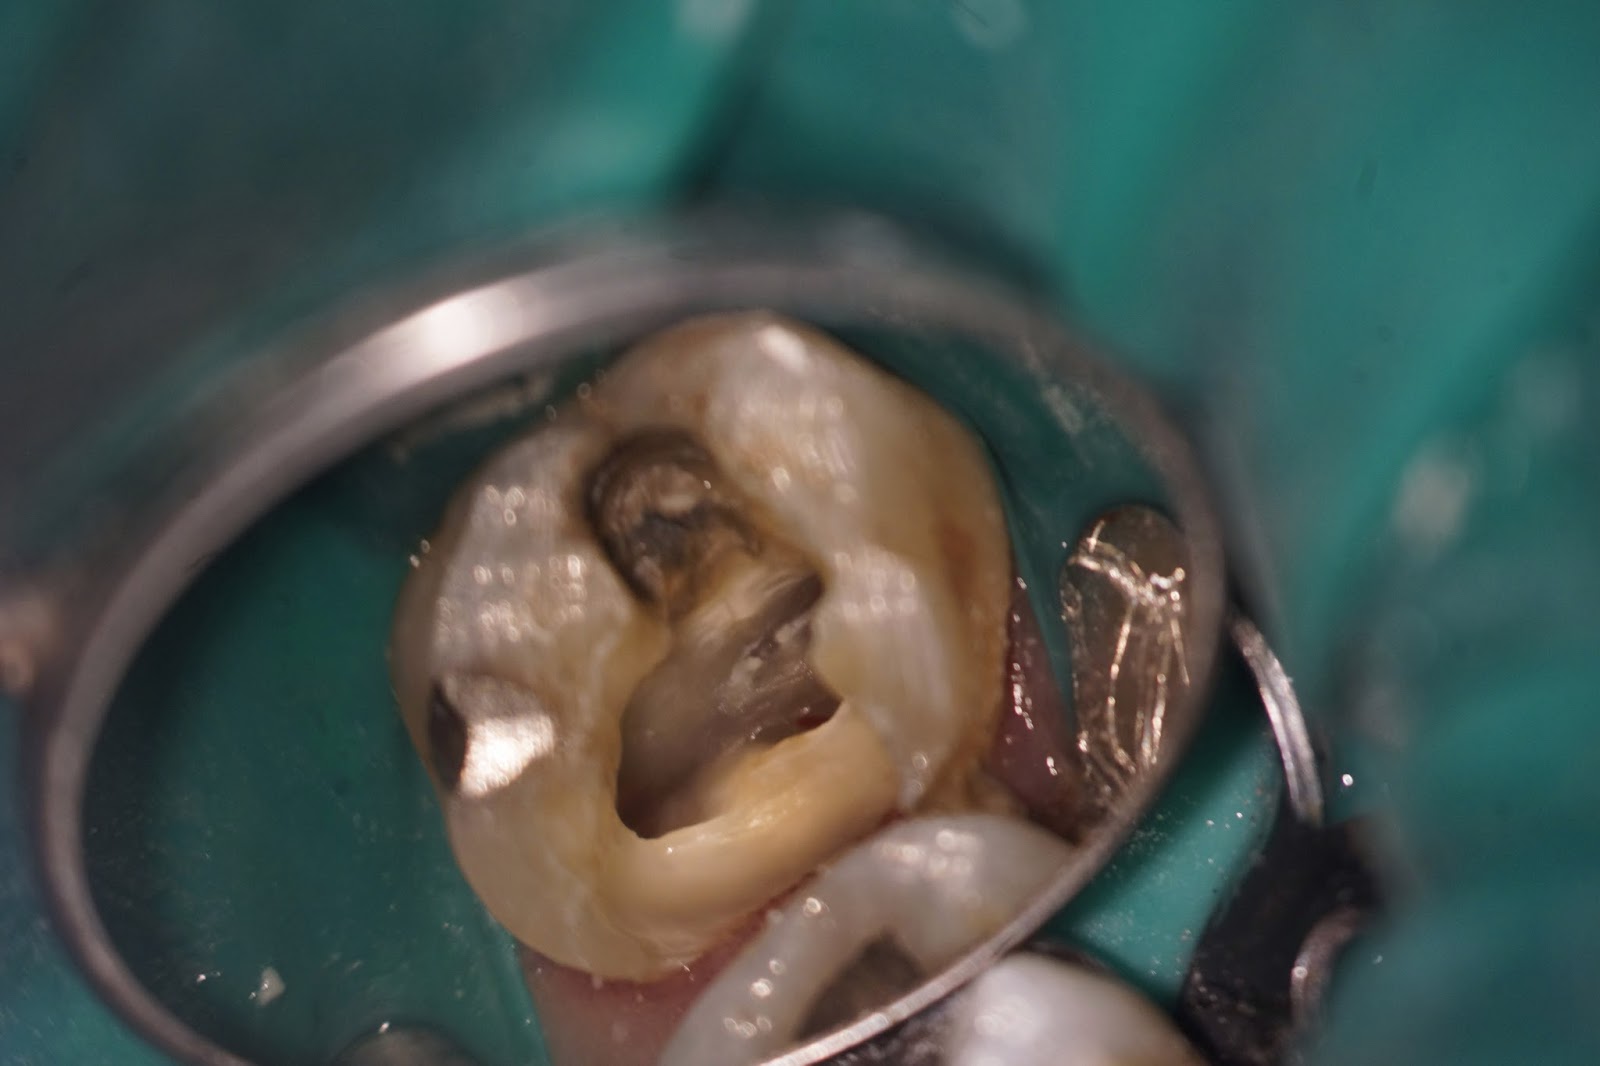

Distal decay is removed, mesial amalgam removed.  Crack identified on the mesial wall of the pulp chamber.

Further excavation reveals the extent of the mesial crack - going below the CEJ and starting to enter the root.  Patient is informed of the extent of the decay and the options: 1. Complete RCT, buildup and crown with guarded long term prognosis 2. Extraction and replacement with implant or bridge  Pt elects extraction in this case.